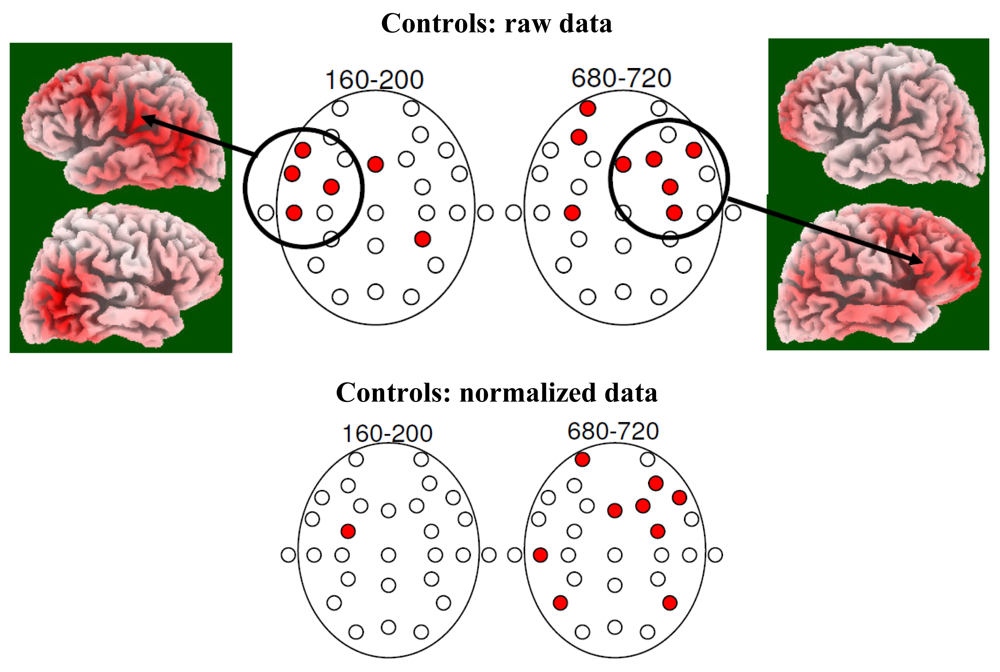

3.2. EEG Data

4.2. Electrophysiology